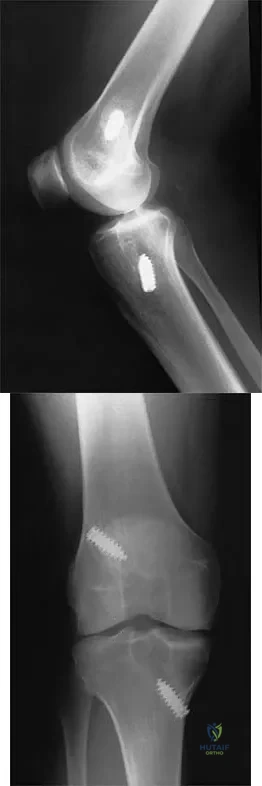

Question 39

A healthy 16-year-old boy has had increasing pain in the right knee for the past 3 months. Examination reveals warmth and swelling around the distal femur. Radiographs and an MRI scan are shown in Figures 51a through 51c, and a biopsy specimen is shown in Figure 51d. What is the most likely diagnosis?

Explanation